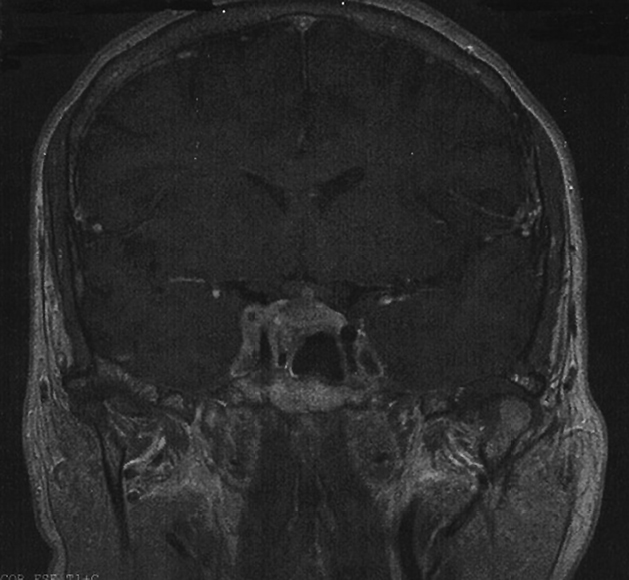

Mujer de 51 años de edad, fumadora de 20 paquetes/año, con antecedentes personales de intervención quirúrgica por gangrena de Fournier hace 20 años y menopausia hace 1 año. Sin antecedentes familiares de interés. Inicia de forma súbita clínica de polidipsia de hasta 10 litros al día junto con poliuria y nicturia. Un mes más tarde comienza con diplopía binocular, hemianopsia bilateral, cefalea y ptosis completa del párpado superior del ojo derecho. Ante la clínica referida es derivada a Oftalmología para valoración, solicitando por su parte una Resonancia Magnética cerebral que se informa como voluminoso macroadenoma hipofisario que invade el seno cavernoso derecho (Figura 1).

Figura 1. Resonancia Magnética que demuestra macroadenoma hipofisario que invade el seno cavernoso derecho.

La técnica de imagen de elección es la Resonancia Magnética. Aunque la evaluación radiológica no diferencia entre lesiones metastásicas y adenomas, hay características como son el engrosamiento del tallo hipofisario, la invasión del seno cavernoso o la esclerosis de la silla turca que pueden orientarnos hacia el origen metastásico en un contexto clínico compatible. El diagnóstico definitivo se obtiene con el estudio anatomopatológico.